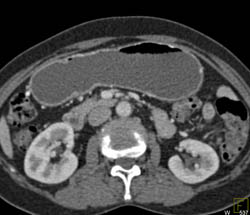

Antral Carcinoma